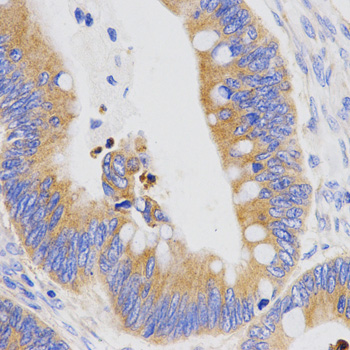

Immunohistochemistry analysis of paraffin-embedded human ovarian cancer tissue using PGC antibody.

Immunohistochemistry analysis of paraffin-embedded human rectal tissue using PGC antibody at dilution of 1:200 (x400 lens).

Immunohistochemistry analysis of paraffin-embedded human stomach cancer tissue using PGC antibody at dilution of 1:200 (x400 lens).